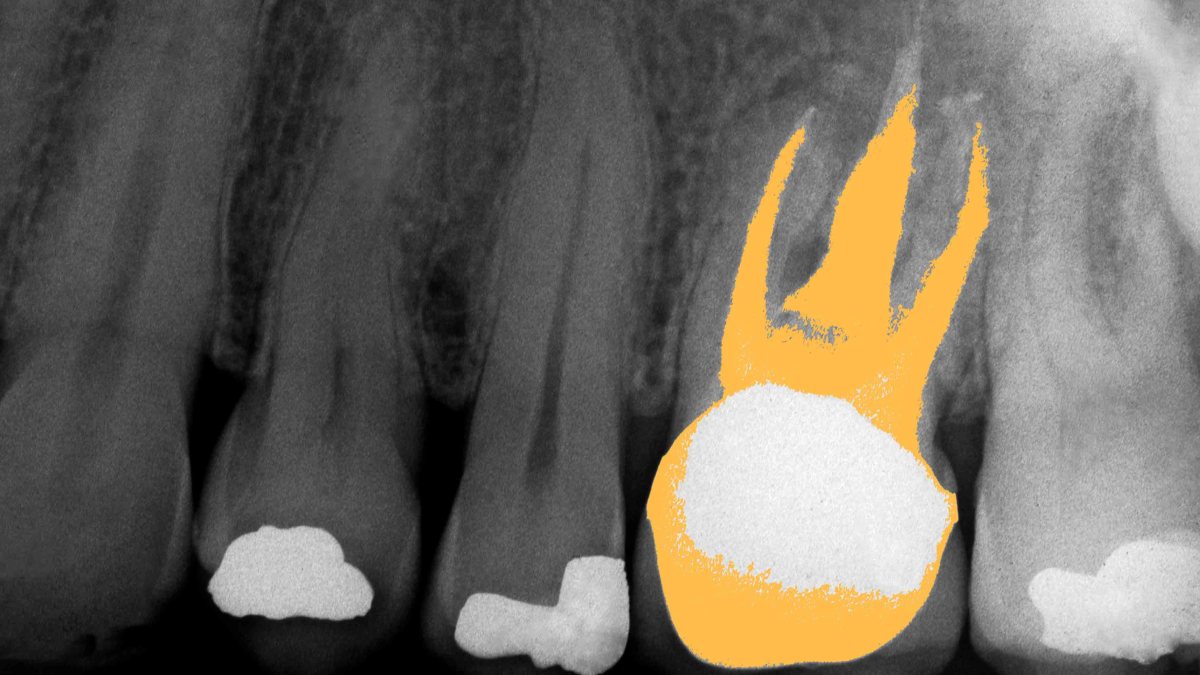

1. When cavities are drilled out, sometimes the fillings don’t stop the decay process. If that goes on long enough, then eventually, the tooth will need to be drilled out/excavated all the way through the root. This removes blood vessels, nerves, and connecting tissue (all of this is known as the pulp). A tooth that has this procedure done to it is effectively dead because the material used in fillings will kill organic cells.